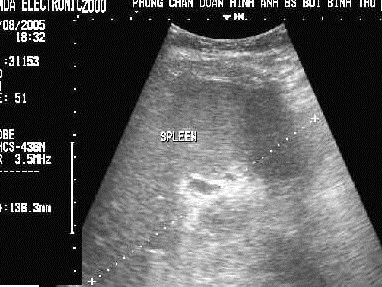

-Splenomegalie :

la rate est hypertrophie > 120mmm , dilatation du

systeme veine hilaire |

La rate augemente de la volume

, sa longeur surpasse 136mm ( normale : 9,5 - 120mm ) . Dilate legerement des veines hilaires . |